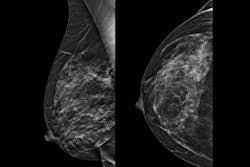

(B) There are scattered areas of fibroglandular density.

(C) The breast is heterogeneously dense, which may obscure small masses.

(D) The breast is extremely dense, which lowers the sensitivity of mammography.